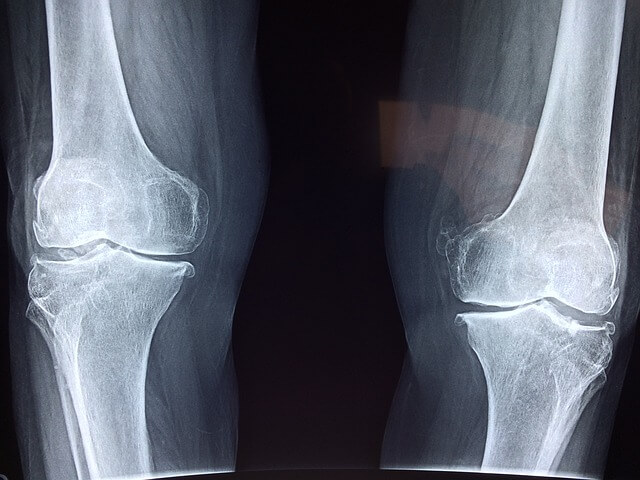

퇴행성 손가락 관절염은 손가락 끝마디에 주로 발생하며, 연골이 닳아 염증이 생기는 질환입니다.

관절염은 관절의 염증을 일으켜 통증과 부기를 초래하며, 손가락 끝마디가 굵어지고 돌출되는 특징이 있습니다.

주로 손을 많이 사용하는 사람들에게 발생하며, 치료에는 진통소염제와 온열치료가 사용됩니다.

2. 류마티스 관절염

류마티스 관절염은 자가면역 질환으로, 손가락 중간 마디와 손가락 시작 부분에 염증이 생깁니다.

손가락이 뻣뻣하고 아프며, 부기와 홍반이 동반될 수 있습니다. 주먹을 꽉 쥘 수 없는 경우도 많습니다. 치료에는 스테로이드, 항류마티스약, 생물학적 제제가 사용됩니다.